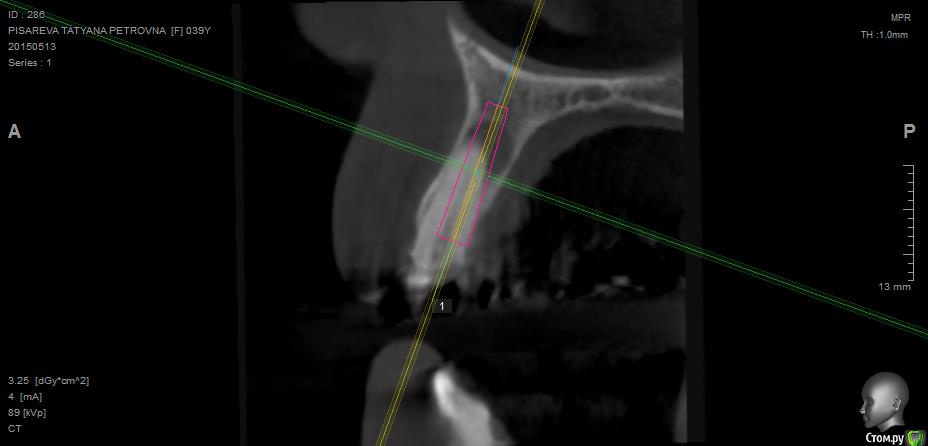

Evikrol Опубликовано 1 мая, 2015 Автор Поделиться Опубликовано 1 мая, 2015 (изменено) Как правильно спозиционировать имплантат? Если есть язычное поднутрение? Это 10, может 8мм? Почему изображение свалилось:-)? Как тут перевернуть:-)) Изменено 1 мая, 2015 пользователем Evikrol Ссылка на комментарий

Evikrol Опубликовано 1 мая, 2015 Автор Поделиться Опубликовано 1 мая, 2015 (изменено) может 8 и не боятся ничего. Да чтож они переворачиваются! Или ауто под надкостницу положить? Изменено 1 мая, 2015 пользователем Evikrol Ссылка на комментарий

faity Опубликовано 1 мая, 2015 Поделиться Опубликовано 1 мая, 2015 область нижней шестерки? по идее 4,5/8 должно хватить, но зачем? ставьте вестибулярнее и 11 войдет на ура до 4,0. Ссылка на комментарий

Evikrol Опубликовано 13 мая, 2015 Автор Поделиться Опубликовано 13 мая, 2015 Можно ли в таком случае одномоментно удалить и поставить? 18 мм если заякорится то и временную. Ссылка на комментарий

Аслан Опубликовано 14 мая, 2015 Поделиться Опубликовано 14 мая, 2015 Я бы не стал ставить винт сразу.Во-первых его надо сместить апикальнее на 3 мм, какараз упрется в кортикалку, Во-вторых. Я бы вышкреб с засыпал под мембрану и стт, но края не сводить, а уж потом винт и коронка сразу. 1 Ссылка на комментарий